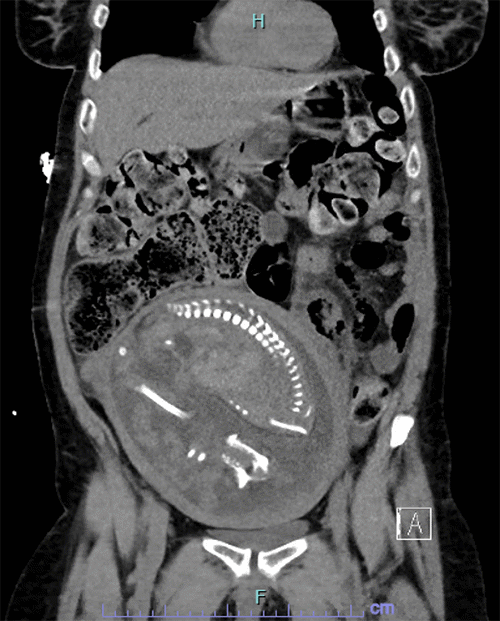

The patient’s condition deteriorated, marked by increasing lethargy, tachycardia, and worsening abdominal signs and symptoms, including peritonitis. Following discussion with maternal-fetal medicine, a CT scan of the abdomen and pelvis was performed, revealing free air and stool in the abdomen (Figure 1). Given these findings, an emergency laparotomy was planned in conjunction with the obstetrics team, with continuous perioperative fetal monitoring.

Figure 1. Abdominal and Pelvic CT Imaging (Axial and Coronal Views) with IV Contrast. Published with Permission

The coronal view confirms significant fecal impaction with multiple air pockets, suggestive of stercoral perforation